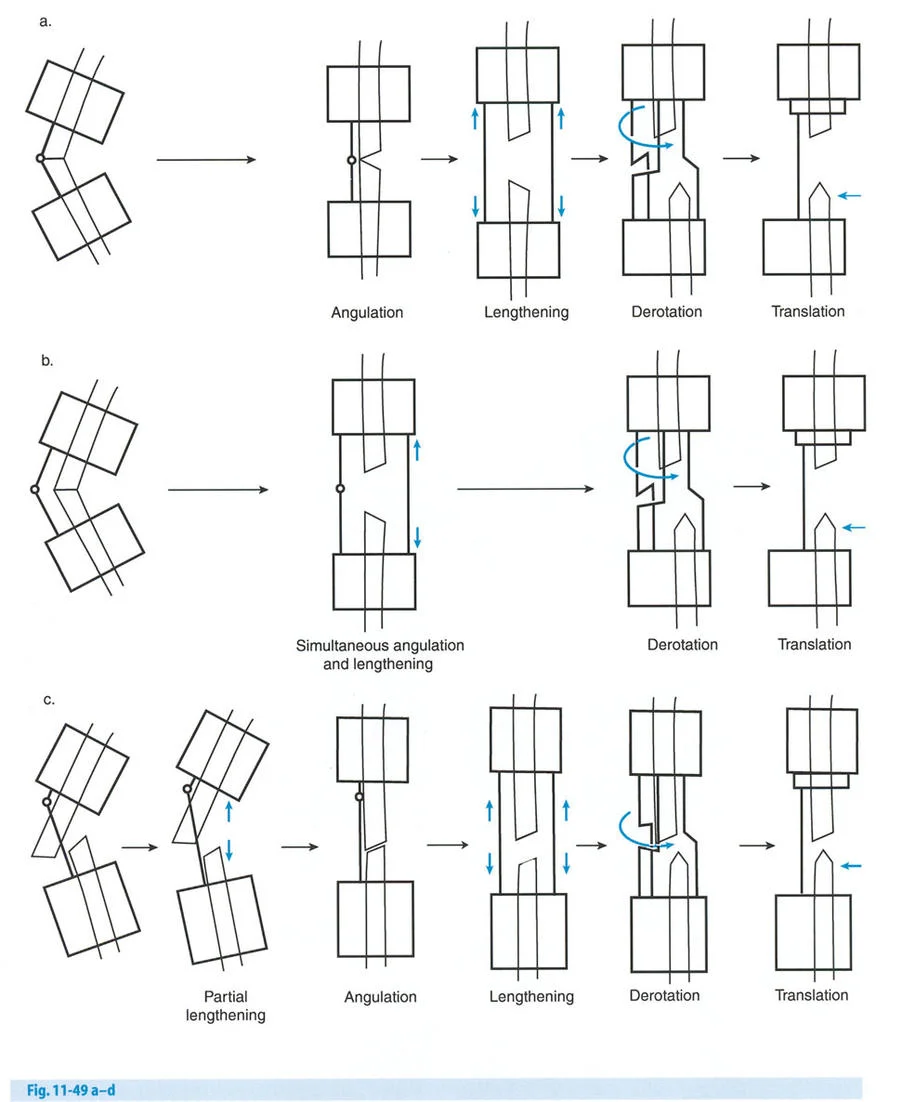

- قاعدة قطع العظم 1: عندما يمر قطع العظم ومحور تصحيح الانحراف (ACA) كلاهما عبر مركز دوران الانحراف (CORA)، فإن نهايات العظم ستنحرف دون ترجمة (انزياح). يتم استعادة المحور الميكانيكي، وتظل نهايات العظم متقاربة تمامًا، مما يخلق تصحيحًا كلاسيكيًا "إسفينيًا مفتوحًا" أو "إسفينيًا مغلقًا".

- قاعدة قطع العظم 2: عندما يمر محور تصحيح الانحراف (ACA) عبر مركز دوران الانحراف (CORA)، ولكن يتم إجراء قطع العظم على مستوى مختلف (غالبًا بسبب ضعف جودة العظم عند CORA أو مشاكل في الجلد)، فإن نهايات العظم ستنحرف وتخضع لترجمة محسوبة ومقصودة لإعادة محاذاة المحور الميكانيكي.

- قاعدة قطع العظم 3: (للاكمال) عندما يمر قطع العظم عبر مركز دوران الانحراف (CORA)، ولكن يتم وضع محور تصحيح الانحراف (ACA) خارج CORA، سيتم إنشاء تشوه ترجمة جديد، وهو خطأ شائع في وضع المفصلات غير المخطط له جيدًا.

في المنشآت القريبة من المفصل، غالبًا ما نعتمد على قاعدة قطع العظم 2. نظرًا لأنه لا يمكننا قطع العظم بأمان عند خط المفصل تمامًا (مركز دوران الانحراف CORA)، فإننا نقطع العظم في مستوى أدنى في منطقة الميتافيسيس. بعد تحقيق التصحيح الزاوي عبر المفصلات (محور تصحيح الانحراف ACA)، يتم إعادة محاذاة خطوط المحور الميكانيكي بشكل مثالي، ولكن نهايات العظم في موقع قطع العظم تتحرك بالنسبة لبعضها البعض.